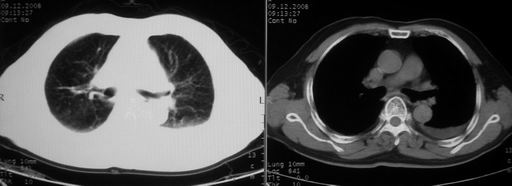

10月9日片:

ct左肺下叶大片状高密度影,病变密度不均,界限不清,左侧胸腔积液,治疗后复查临床症状好转而影像学表现病变有发展,还是首先考虑感染性病变,复查时间短附合感染性病变的病理改变。